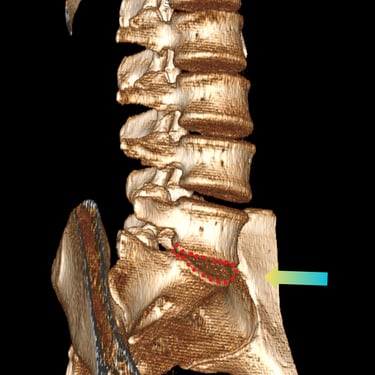

🧠 Listesis L4–L5 con Estenosis Severa: Estabilización con Fijación Transpedicular (FTP) y Fusión Intersomática Transforaminal (TLIF)

La listesis L4–L5 con estenosis severa provoca dolor lumbar e inestabilidad con compresión nerviosa. La fijación transpedicular (FTP) y la fusión intersomática transforaminal (TLIF) permiten descomprimir el canal espinal, estabilizar la columna y mejorar la función de forma segura y progresiva.